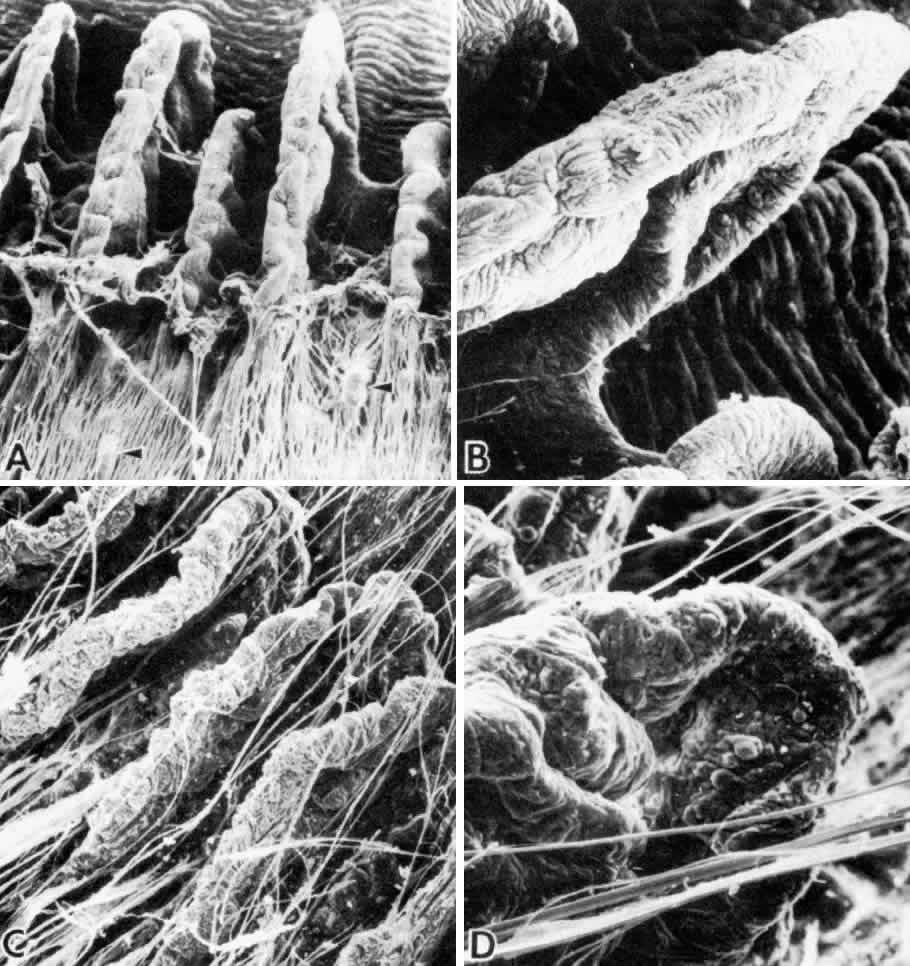

Fig. 13. Ciliary nonpigmented epithelium. A. Anterior pars plicata, age 3. (hematoxylin-eosin, X 800) B. Posterior pars plicata with areas of thickened, pigmented

epithelium, age 3. m, ciliary muscle (hematoxylin-eosin, X 800) C. Nodular

proliferation of the nonpigmented epithelium appears

as small cellular caps over the surface at age 70. Z, zonule. (hematoxylin-eosin, X 400) D. Distorted epithelium of pars plana shows evidence

of traction in both anterior and posterior directions (adult). (hematoxylin-eosin, X 400) Fig. 13. Ciliary nonpigmented epithelium. A. Anterior pars plicata, age 3. (hematoxylin-eosin, X 800) B. Posterior pars plicata with areas of thickened, pigmented

epithelium, age 3. m, ciliary muscle (hematoxylin-eosin, X 800) C. Nodular

proliferation of the nonpigmented epithelium appears

as small cellular caps over the surface at age 70. Z, zonule. (hematoxylin-eosin, X 400) D. Distorted epithelium of pars plana shows evidence

of traction in both anterior and posterior directions (adult). (hematoxylin-eosin, X 400)